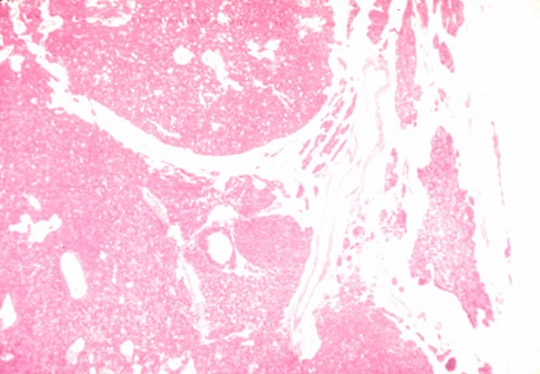

- Parathyroid adenoma:

a microscopic section of the parathyroid gland reveals an adenoma. The neoplasm is composed of sheets of uniform cells displacing adipose cells. The expanding neoplasm compresses adjacent normal parathyroid tissue.

Dr Ralph Leischner